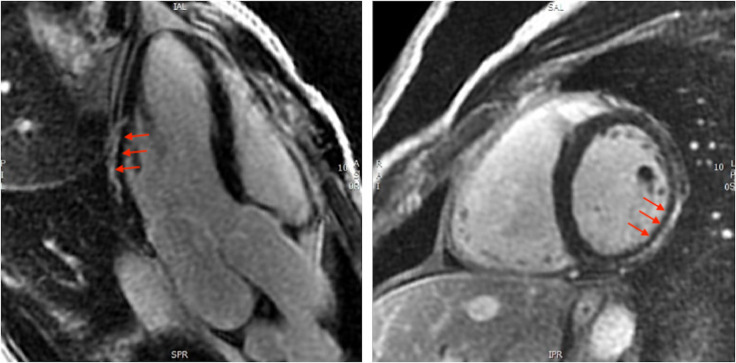

Background: Myocarditis is a rare but potentially serious complication of COVID-19 vaccination. Cardiac magnetic resonance (CMR) with late gadolinium enhancement (LGE) imaging can identify cardiac scar, which may improve diagnostic accuracy and prognostication. We sought to define the incidence of long-term LGE post COVID-19 vaccine-associated myocarditis (C-VAM) and to establish the additive role of CMR in the diagnostic workup of this condition.

Results: 67 patients with C-VAM (mean age 30±13 years, 72% male) underwent CMR evaluation. The median time from vaccination to CMR was 548 (range 398-603) days. 20 patients (30%) had LGE. At diagnosis, nine patients (13%) were classified as definite and 58 (87%) as probable myocarditis. With the integration of CMR-LGE data, 16 patients (28%) were reclassified from probable to definite myocarditis.

Conclusion: LGE on CMR occurred in one-third of patients with C-VAM. Without CMR at the time of diagnosis, almost one-third of patients are misclassified as probable rather than definite myocarditis, indicating a diagnostic strategy using echocardiography alone is insufficient.